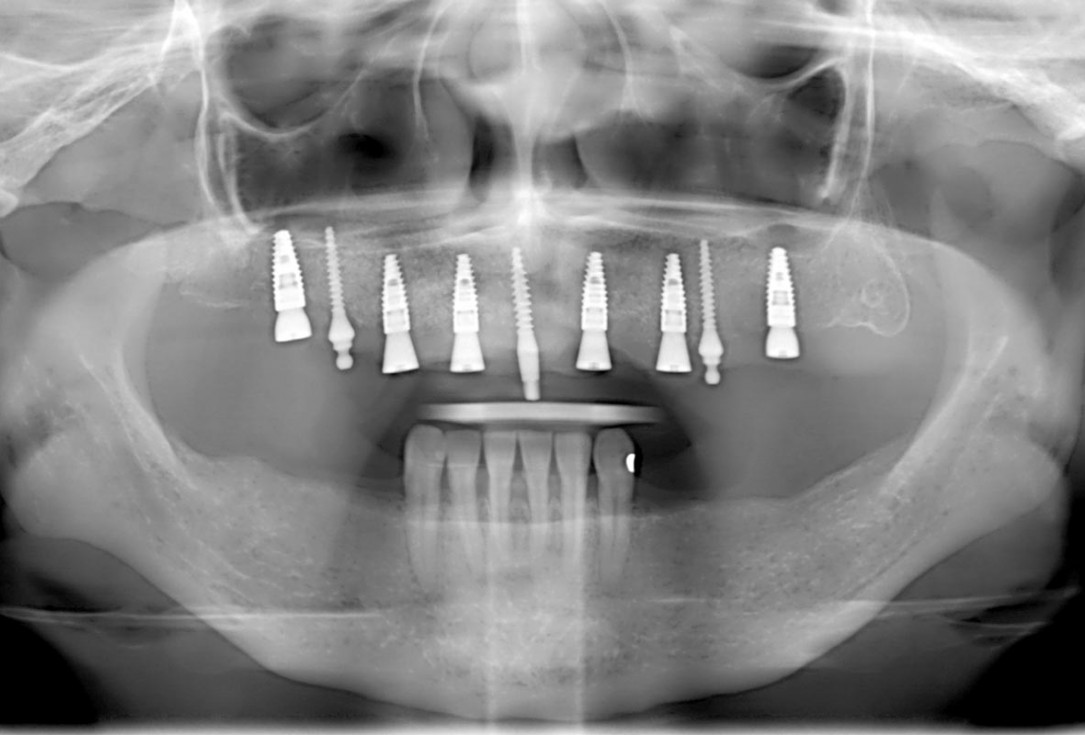

Initial x-ray showing bone loss around implants placed 5 years ago in another dental clinic